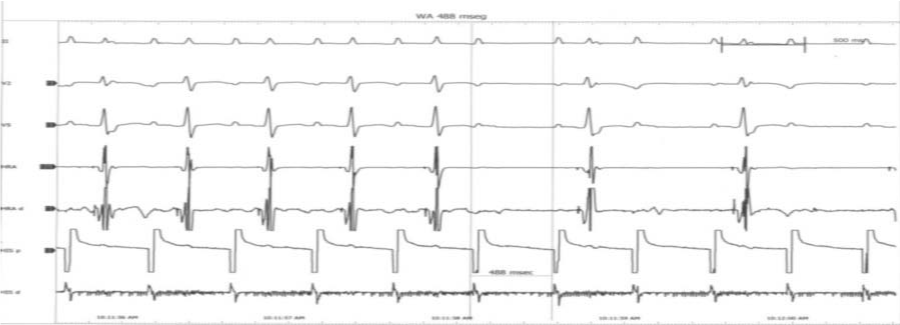

Figure 2 Patient in Supra-ventricular Tachycardia.

Figure 3 ECG was taken after administration of 12 mgs of Adenosine. Heart rate value is 67-68 beats per minute: Accelerated atrioventricular stimulation with an early and shortened ventricular repolarization. Can be seen a short PQ interval (<0120 seconds) with an early and shortened ventricular repolarization (QTc <0.350. seconds).

A paroxysmal supraventricular tachycardia and Crisis of anxiety. The patient was transferred to our Hospital because he had had a similar event as the exposed, after the first visit with his outpatient cardiologist. There, the patient was adequately assessed with electrocardiogram, echocardiogram, blood levels of ions and cardiac markers as well as electro-physiological study (EEF) (Figure 4). He was negative for high levels of Troponin (I-T), CK, CPK-MB and however he was positive for a low levels of lithium ion (<0.1 mEq/L) In a detailed assessment on ECG, we can note that the patient has a short PQ- interval with a short QTc in the same ECG tracing (Bazett and Fridericia formulas) with a risk of sudden cardiac death, according to the Schwartz scale12 of 4.5 points: High risk for sudden cardiac death. At first glance, the ECG tracing interpretation suggests a syndrome Lown - Ganong - Levine, but in a more detailed checkup we see as the QTc interval in the LGL syndrome is normal while in this patient, the QTc interval is short (<0.350 s). We have therefore two possibilities: an unknown variant of LGL Syndrome or a new electrical cardiac disease.

Both PQ and QT intervals are short (Figure 3-5).

Figure 5 Holter Image: Same features than Figure 1. PQ-interval: 0.100-0.110 seconds=Short PQ-interval. QTc (Bazzet) 0.339-0.340 seconds (< 0.350 seconds) = Short QT-interval. QTc (Fridericia) 0.332 seconds (< 0.350 seconds) = Short QT-interval.

PQ- interval: 0.10 - 0.11 seconds. RR- interval: 0.862- 0.900 seconds. QT- Interval:0.322-0.330 seconds. Bazett’s formula: 0.339-0.343 seconds. Fridericia’s formula: 0.330-.337 seconds.